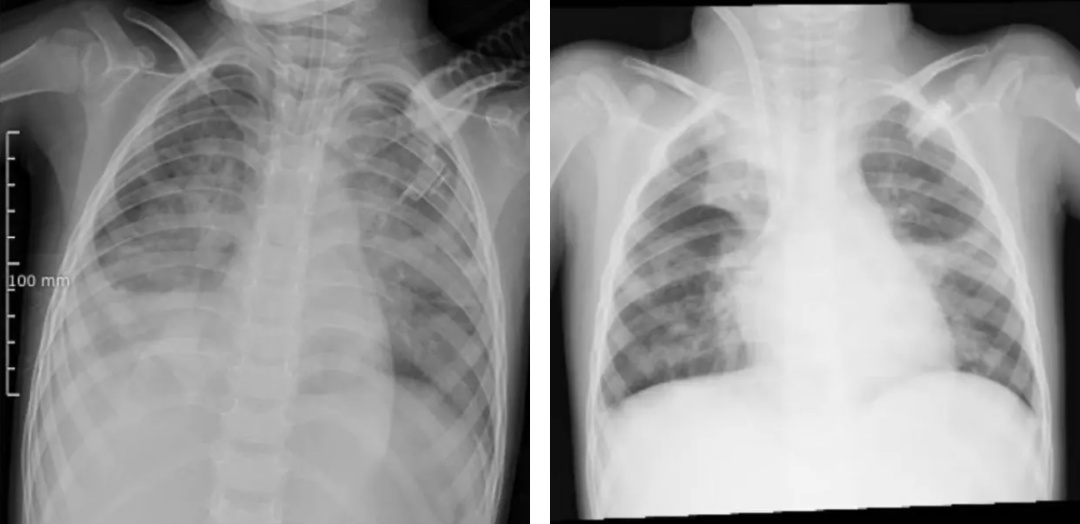

图源 河南省儿童医院(左图为ECMO上机前,肺部结构模糊,呈现“白肺”影像表现。右图为ECMO支持治疗5天后,肺部影像清晰度明显改善)

检查结果令人揪心:甲型流感病毒(H3N2)、金黄色葡萄球菌、流感嗜血杆菌,形成“病毒牵头、细菌跟攻”的“三重打击”,引发严重肺部感染,发展为急性呼吸窘迫综合征(ARDS),生命悬于一线。

当地医院医疗团队几乎使用了所有常规治疗手段:有创呼吸机、高频振荡通气、一氧化氮吸入……然而,即使在极高的呼吸机参数支持下,朵朵的血氧饱和度仍仅能维持在80%-85%,呼吸衰竭难以纠正。

在常规治疗无效、命悬一线之际,河南省儿童医院ECMO团队携“人工肺”紧急跨市驰援,成功建立生命通道,完成了一场与时间赛跑的生死救援。上机一周后,经全面评估各项指标,朵朵顺利撤离ECMO,转入后续康复治疗阶段。